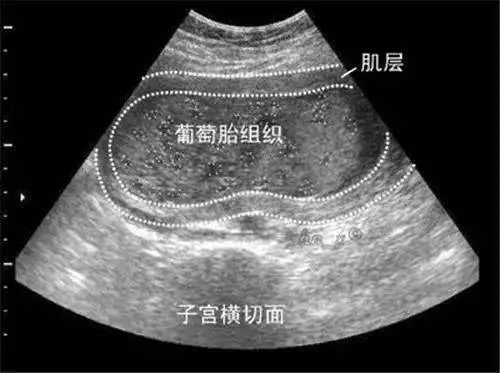

葡萄胎是指怀孕后滋养细胞不规则增生、绒毛间质水肿,每一个水泡,就是一根水肿的绒毛,许多水泡连在一起,看上去就像一串串葡萄,因而称之为葡萄胎。

葡萄胎一般在怀孕40~50天左右到医院做B超就可以发现,停经后阴道流血是葡萄胎最早和最常见的症状,发生率一般在98%以上。

多数患者在停经2~4个月后发生不规则阴道流血,多为持续少量,以后逐渐增多,反复发作,或连绵不断,患者有贫血现象。偶尔可在流出的血中发现水泡状物。而且由于葡萄胎增长迅速,子宫快速过度扩张,孕妈的肚子比一般正常孕周要大得多。